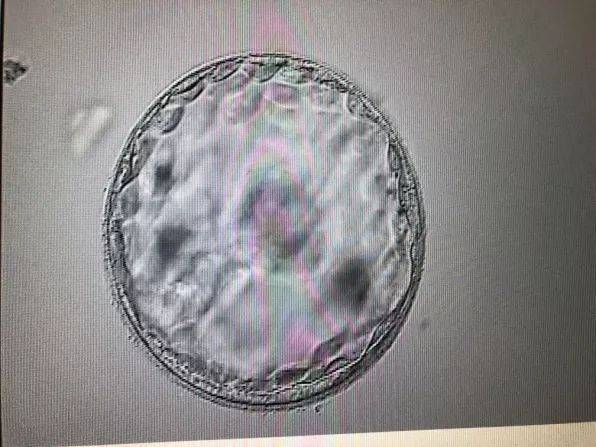

试管婴儿技术,又称体外受精-胚胎移植(IVF-ET)技术,是一种辅助生殖技术。该技术通过将女性卵子和男性精子在体外进行受精,然后将受精卵培养成胚胎,再将胚胎移植回女性子宫内,使其着床发育成胎儿。

取卵后,医生会将卵子和精子放入培养皿中,进行体外受精。受精后,受精卵将在实验室中培养3-5天,成为胚胎。这一过程需要3-5天的时间。